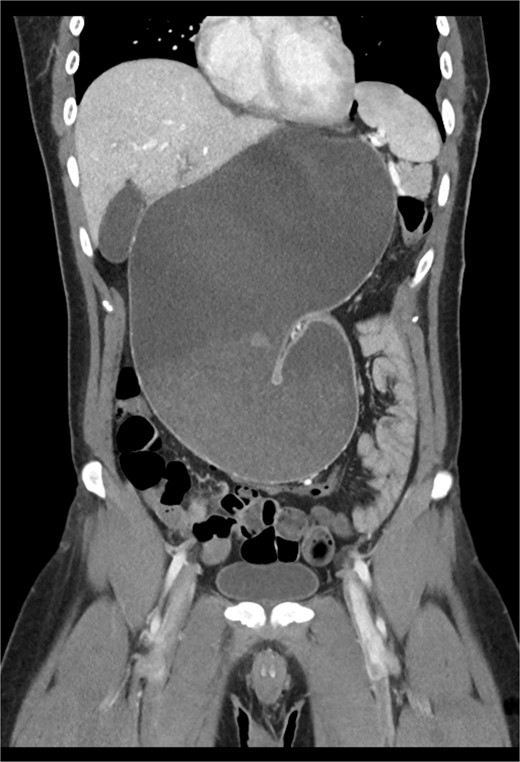

The early postoperative course was unremarkable. The patient reported feeling mild bloating, but was discharged on postoperative Day 1 after removal of a chest tube (Fig. 4). A few hours after discharge from the hospital, he developed dysphagia, progressive abdominal pain, distension, and dyspnea that prompted a return to the hospital. Physical examination revealed tachycardia (132 bpm), mild hypoxia requiring supplemental O2 at 2 L/min via nasal canula, and abdominal distension. Laboratory studies showed WBC of 12 600 cells/μL. A CT scan of the abdomen and pelvis revealed a large, acute organo-axial gastric volvulus without evidence of ischemia, and an intact left hemidiaphragm plication at a similar height to the right hemidiaphragm (Fig. 5). A nasogastric tube was placed with immediate drainage of 1 L of dark bilious fluid with immediate relief of the patient’s symptoms. However, a subsequent film revealed the nasogastric tube projecting toward the upper left chest with presence of colonic haustra (Fig. 6), consistent with acute hemidiaphragm rupture.

CT revealing intact diaphragm plication with massive organo-axial gastric volvulus.